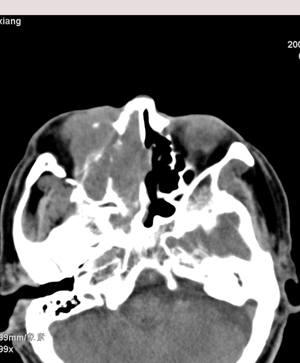

以下是引用影象小辈在2008-5-4 13:34:00的发言:[br]鼻腔及右侧上颌窦 筛窦内软组织密度影, 相邻鼻中隔、鼻甲及窦壁骨质破坏吸收,病灶延伸至鼻咽腔及右侧眼眶 多考虑为1.乳头状瘤 2.息肉 建议增强及活检

以下是引用peijunlong在2008-5-4 13:35:00的发言:[br]考虑右侧鼻腔内翻性乳头状瘤[br]好发:中老年人。[br]ct:1:一侧鼻腔内肿块经扩大的自然孔道长入鼻窦,是其顺自然孔道蔓延的特点[br] 2:鼻腔,鼻窦扩大,窦壁压迫性骨质破坏。[br] 3:广泛生长的肿瘤可侵犯邻近结构,如眼眶、翼腭窝和颅内。

以下是引用不学无术在2008-5-4 20:43:00的发言:[br]病人已在齐鲁医院穿刺活检病理结果:中分化鳞癌。